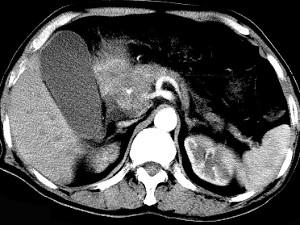

问题 男50岁黄疸进行性加重、腹部胀痛不适、食欲减退、体重减轻、上腹部可触及肿块,CT如图,最可能的诊断为 ( )

选项 A、腹膜后淋巴瘤 B、转移瘤 C、慢性胰腺炎 D、胰头癌 E、急性胰腺炎

答案 D